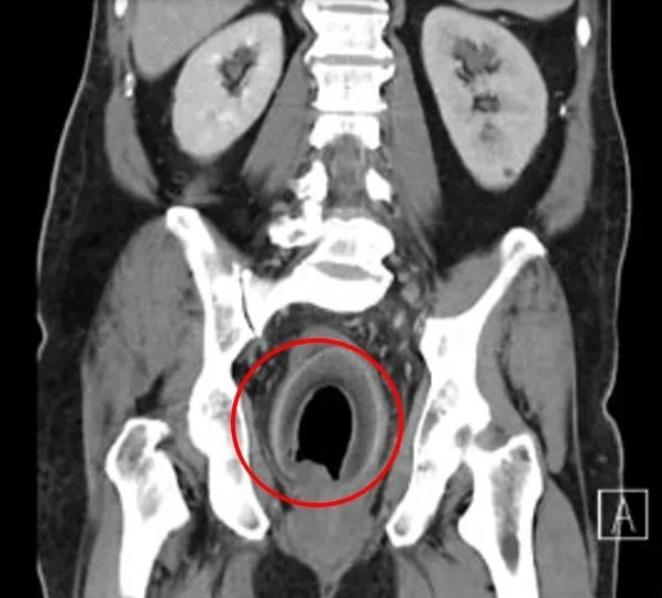

綜合報道,高雄義大醫院一般醫學外科主任、大腸直腸科主治醫生陳致一坦言,這是第一次碰到塞椰子的個案。他表示,男子是獨自求診,聲稱前一晚塞了東西入肛門裡,膀胱很漲,未能排尿,經電腦掃描(CT)發現,男子的膀胱漲到有如一個橄欖球,估計裡面大概有近2,000毫升的尿,幾漲爆,另外直腸也有個圓形異物,向男子查詢後,對方回答:「椰子」。醫護試過先為男子導尿,但被椰子卡住,尿管插不入膀胱,再試過用手及多種器械,伸進去男子肛門,但無論怎麼夾、怎麼挖,椰子仍是原封不動。經過評估,倘若繼續拖延下去,恐會膀胱爆破、直腸壞死,陳致一立即進行手術,以類似「剖腹產」的方式,剖開直腸取出椰子。但到底如何將椰子塞入肛門,男子直至出院仍不願透露。

陳致一指,肛門塞異物最可能的危險,就是造成肛門撕裂傷,恐留下括約肌鬆弛、滲便的後遺症,再者異物也可能傷害直腸組織,可能被塞傷、塞破,而上述男子所塞的椰子,更是卡住膀胱出口,還有膀胱漲破的風險,奉勸有此習慣者,還是不要「逆其道而行」,以免後悔莫及。網上圖片顯示,那個取出的椰子的長度有約10厘米。